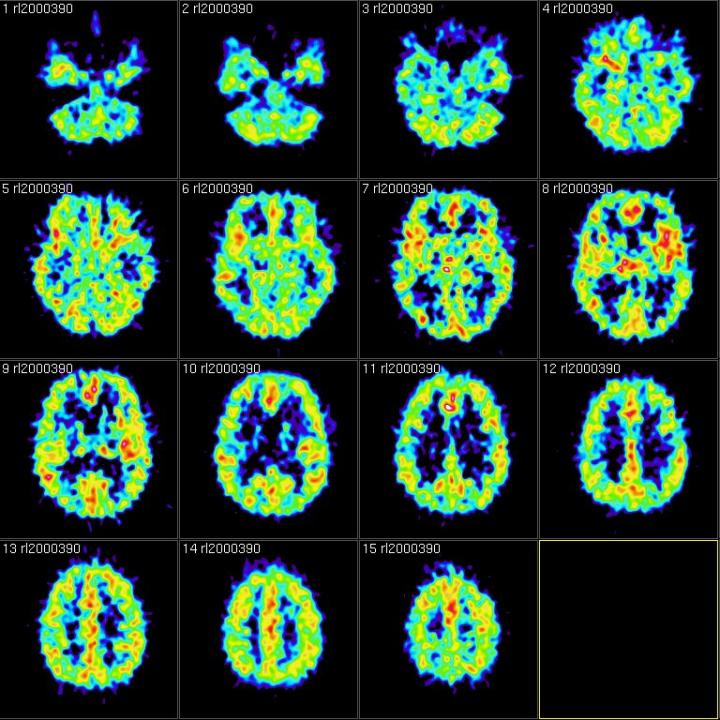

When the group was told to forget, the brain scans showed that they literally “flushed out” the scene from their brains.